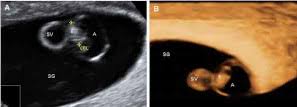

Recordemos que en esta semana el embrión tiene cuatro semanas de edad ya que habitualmente al contabilizar las semanas de embarazo se empieza desde la. Aproximadamente 6 semanas más o menos en el embarazo los latidos del corazón del feto se pueden detectar a través de un ultrasonido que sin embargo puede variar mucho en situaciones reales.